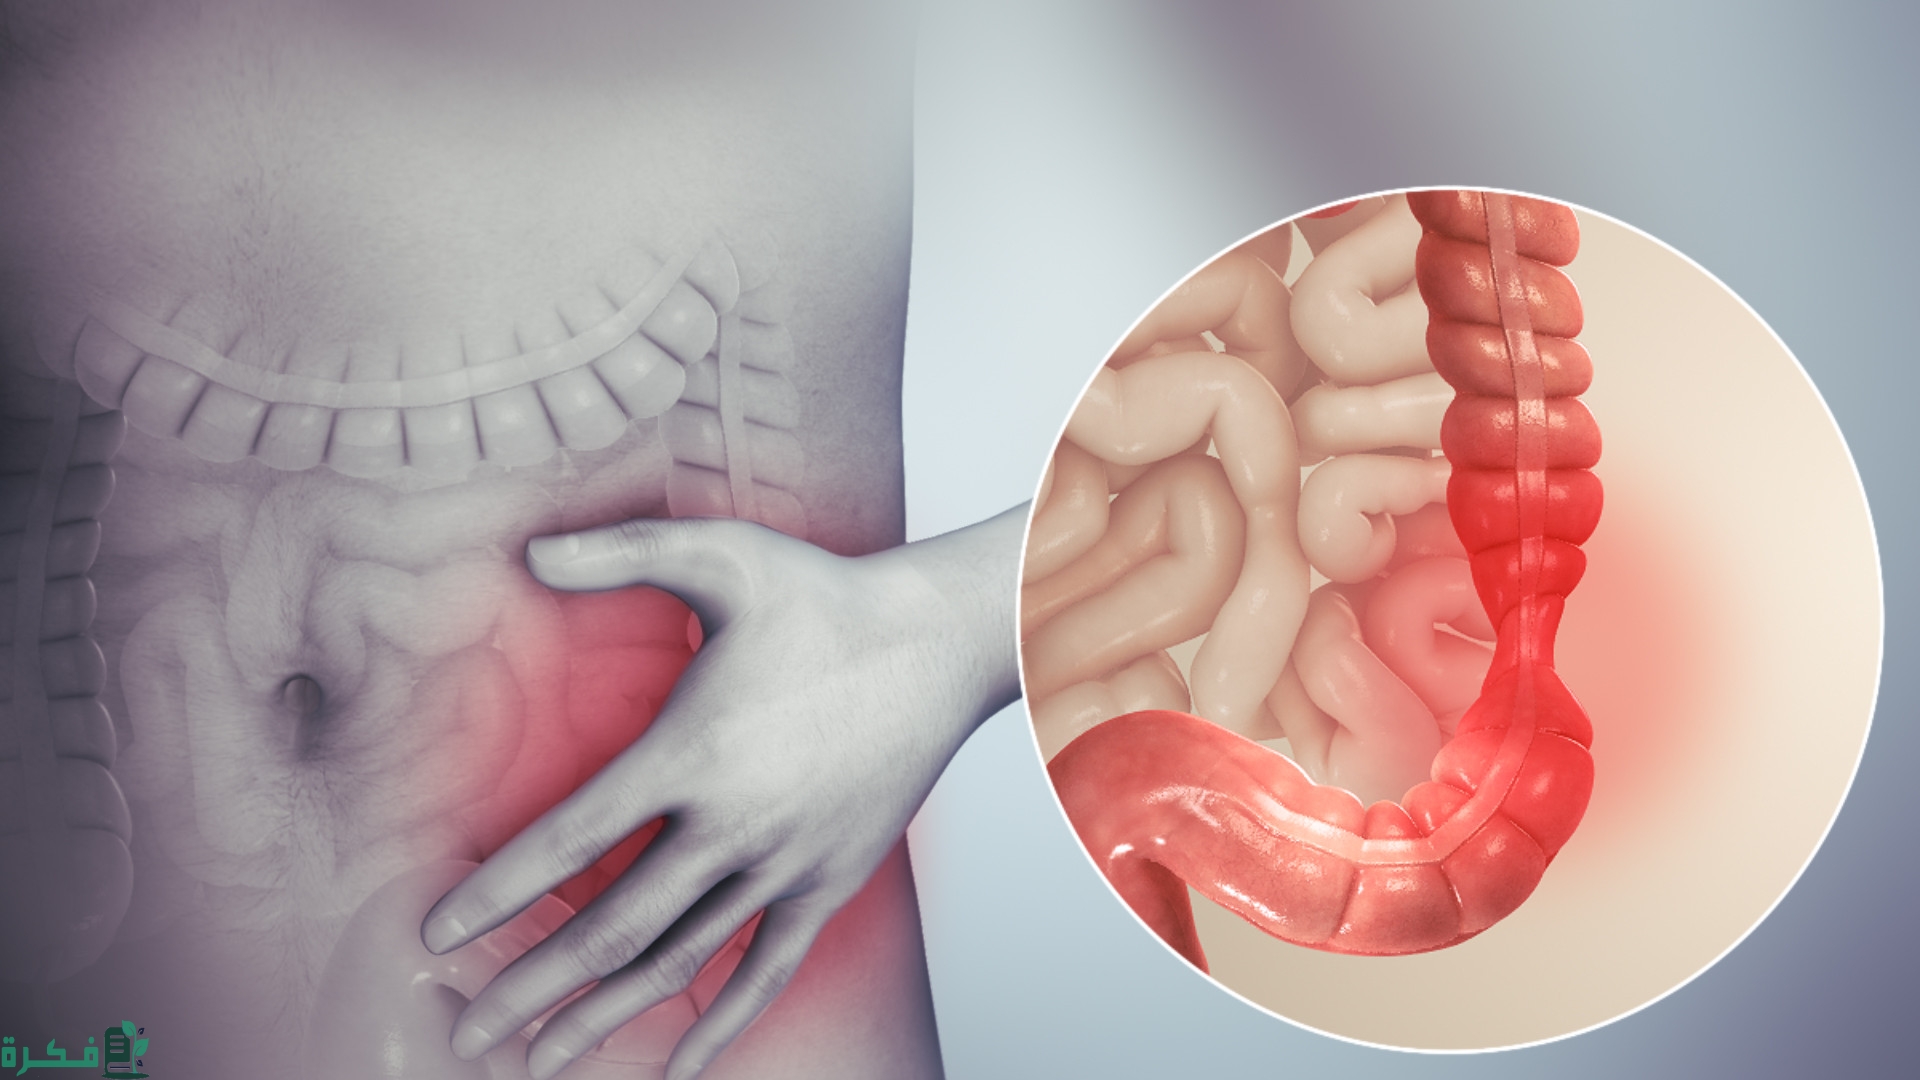

أكمل القراءة »أفضل 5 أدوية علاج التهاب الاثنى عشر يبحث عنه الكثير من المرضى الذين يعانون من التهابات في الجهاز الهضمي والمصابين…